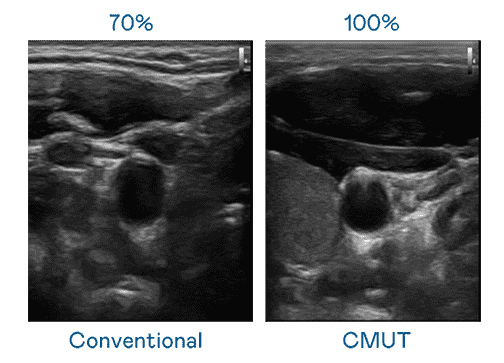

CMUT 技术是一种用电容式微机电元件来产生超音波讯号的技术。。。。与传统 PZT 压电式技术相比,,,CMUT 频宽增加 30%,,,更宽频的超音波讯号让影像解析度大幅提升,,,,是实现高影像品质医疗超音波扫描、、、促进精准医疗发展的关键技术。。。

大频宽带来超清晰影像

超音波影像的解析度高低,,,,首先取决于探头能发出的讯号频宽。。。888.BY集团电子游戏 CMUT 可提供高清晰的超音波讯号,,,,提供高频宽、、高灵敏度、、、、影像纹理细节更高的超音波影像,,,,协助医护人员缩短影像判读时间及利用精准的医疗影像进行诊断。。